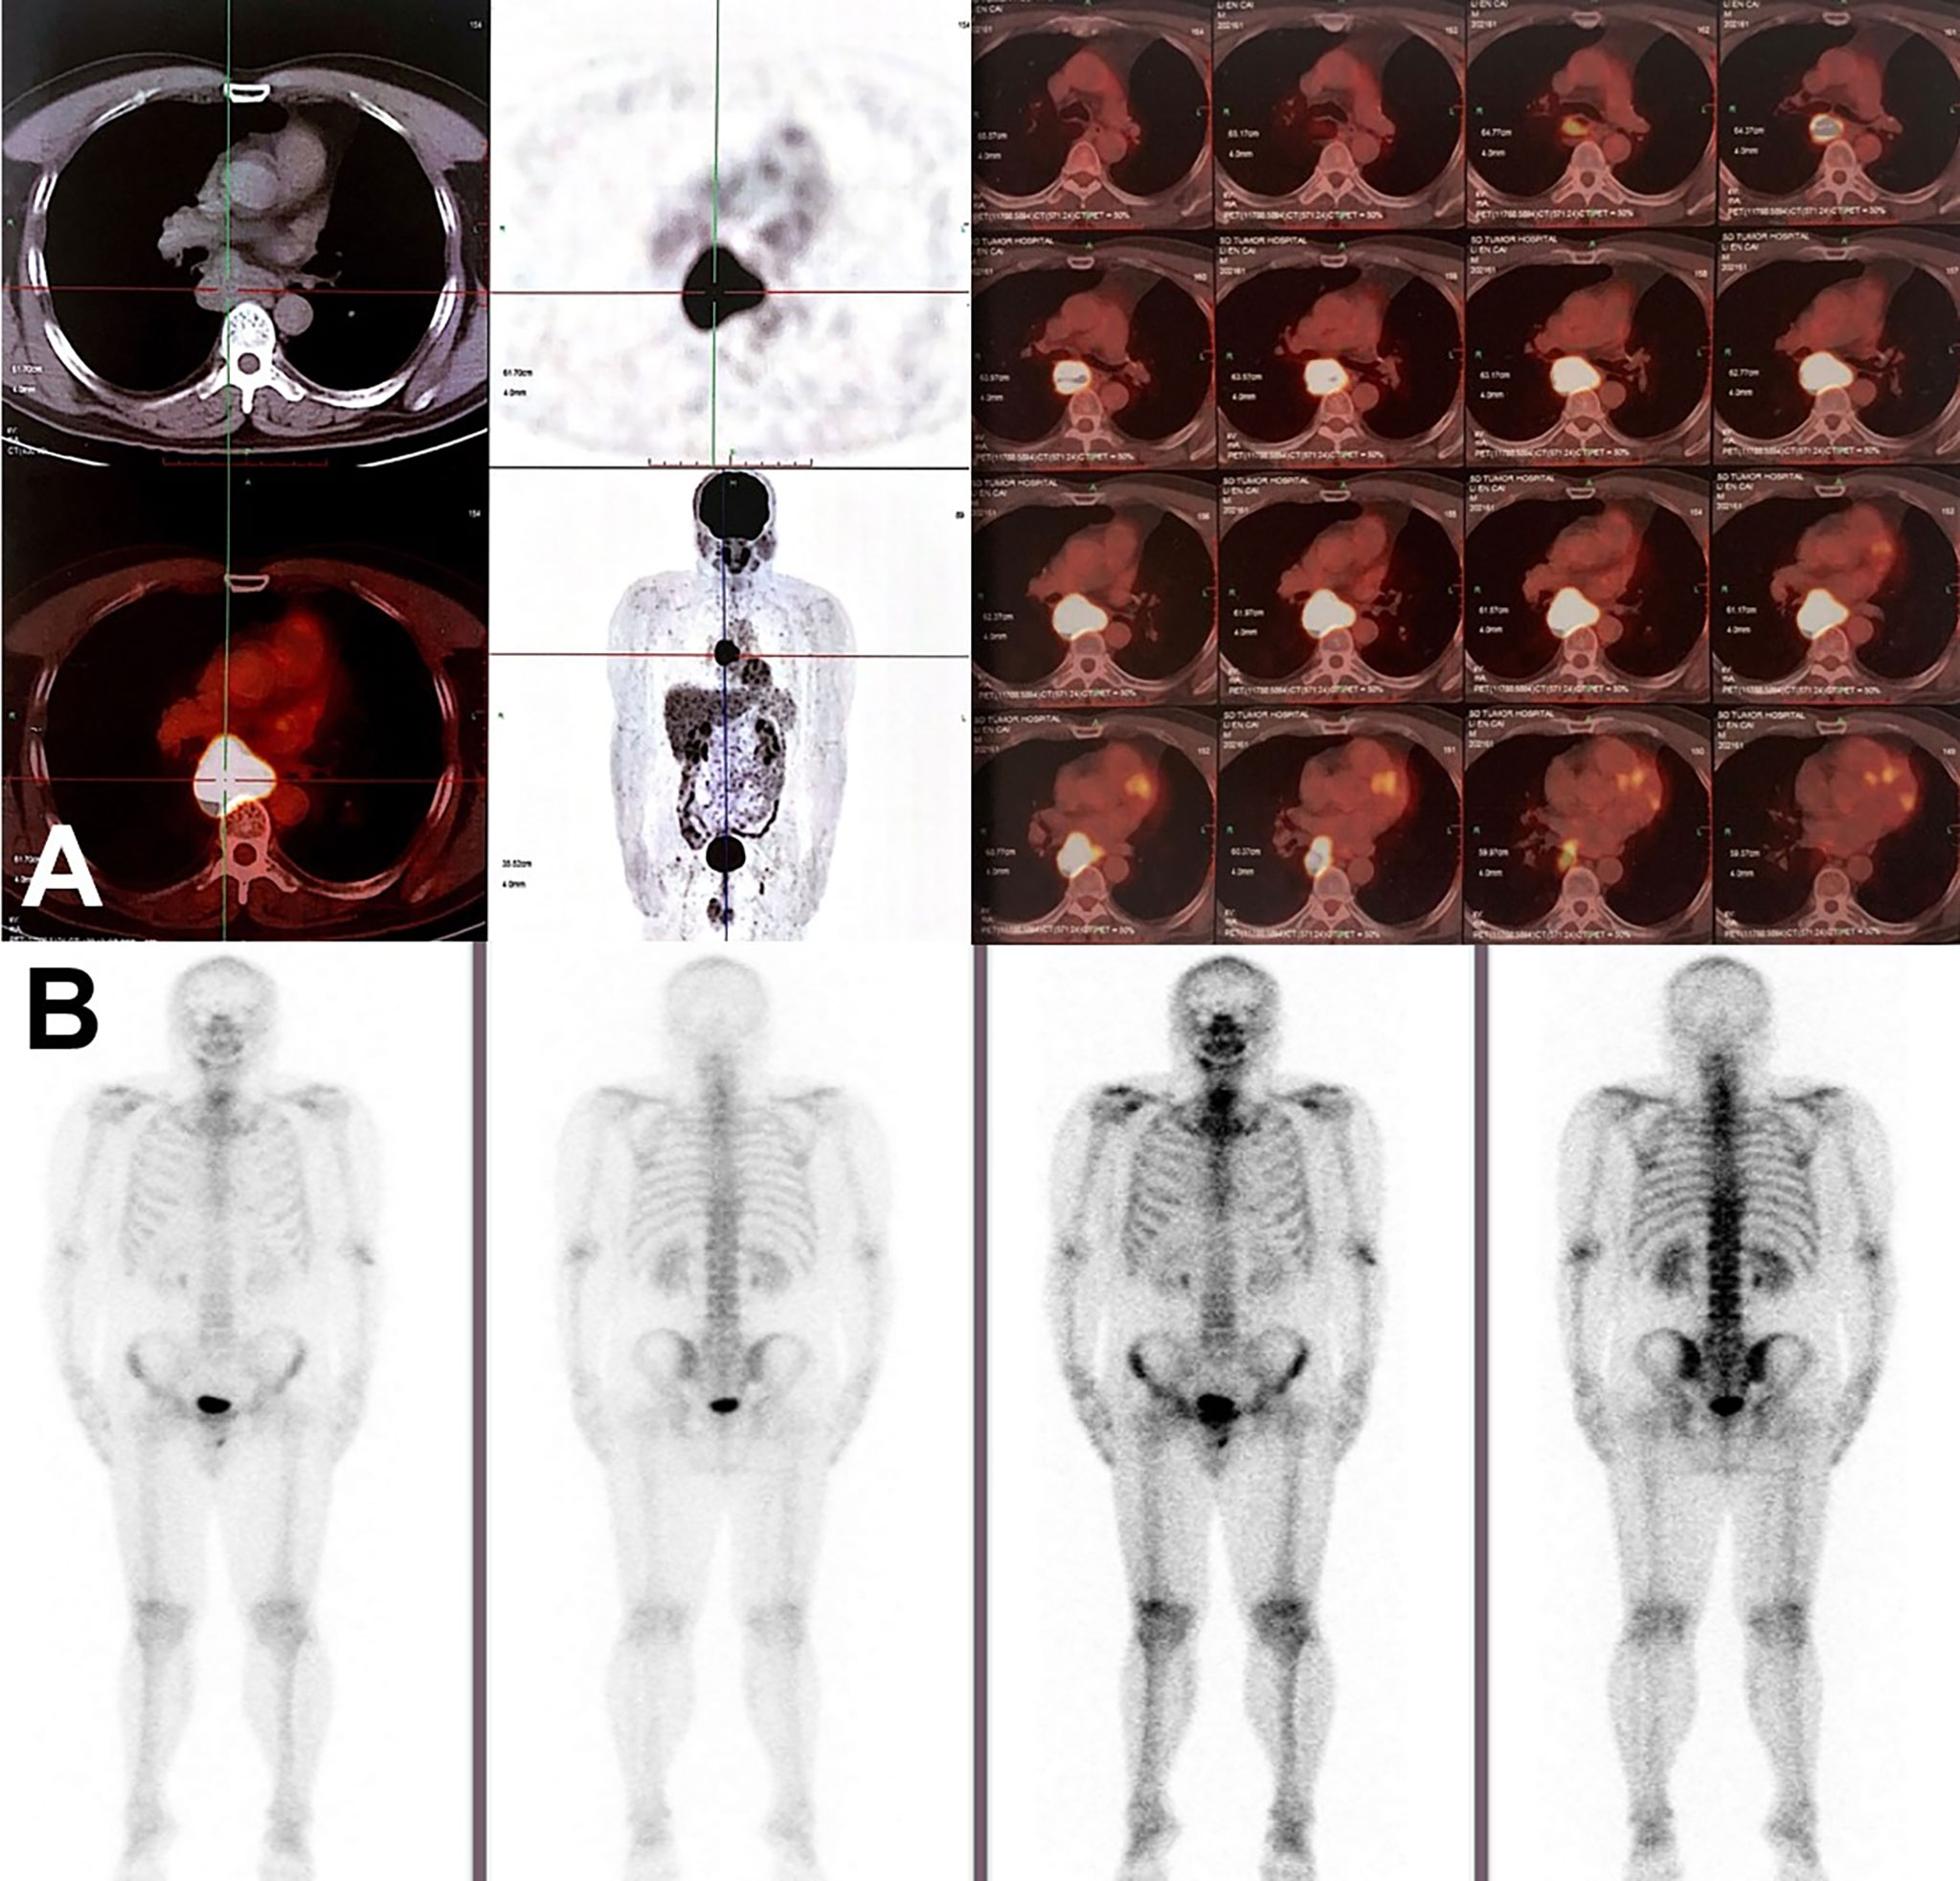

On June 18, 2020, 2 years after the left lung bullae resection, CT scan demonstrated an irregularly enlarged mediastinal lymph node station 7 with heterogeneous enhancement, about 5.2 cm * 4.7 cm, considered as the metastasis, but no visible primary pulmonary parenchymal focus (Figures 1A, B). Subsequent bronchoscopy did not reveal any primary lung lesion either. Positron emission tomography (PET)/CT suggested the enlarged mediastinal lymph node station 7 with increased 18F-fluorodeoxyglucose (18F-FDG) uptake and unclear boundary with adjacent esophagus. The corresponding maximum standardized uptake value (SUV) of the enlargement was 22.2, and it was considered a metastasis possibly from a pulmonary origin, while no obvious pulmonary lesion with positive 18F-FDG uptake was found (Figure 2A). Hence, unexpectedly, the primary lesion remained unclear even after PET/CT. No evidence of distant metastasis emerged after performing PET/CT, brain MRI, and whole-body radioactive bone scan (Figure 2B). Physical examination (PE) also was negative.

Figure 2 Radiographic findings on PET/CT and radioactive bone scan. (A) PET/CT scan in June 2020 showed the enlargement of mediastinal lymph node station 7 with max SUV 22.2, suggesting mediastinal lymph node metastasis. No visible primary pulmonary parenchymal focus but postoperative changes in the left lung. (B) No distant metastasis on radioactive bone scan.